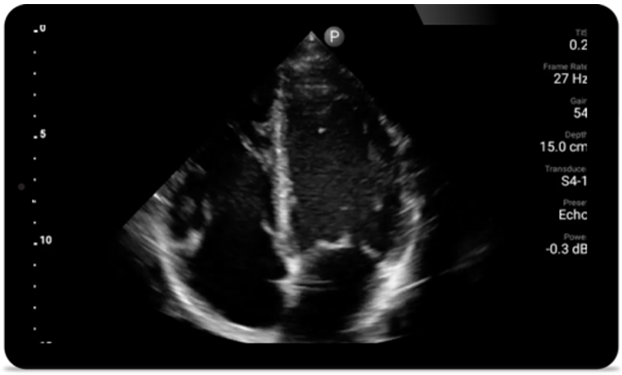

Cada segundo cuenta en la atención cardíaca

Los pacientes que sufren un ataque cardíaco necesitan atención inmediata. Los ajustes cardíacos preestablecidos de Lumify pueden ayudar a los pacientes a ser diagnosticados más rápido para mejorar sus resultados.